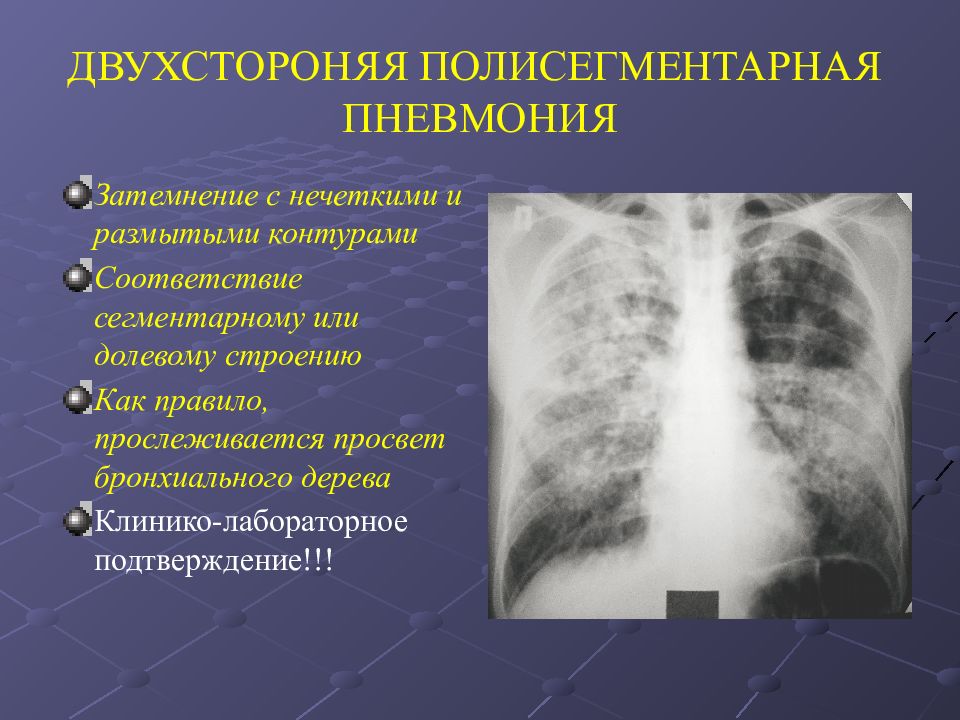

Острая внебольничная пневмония по МКБ-10: признаки и примеры